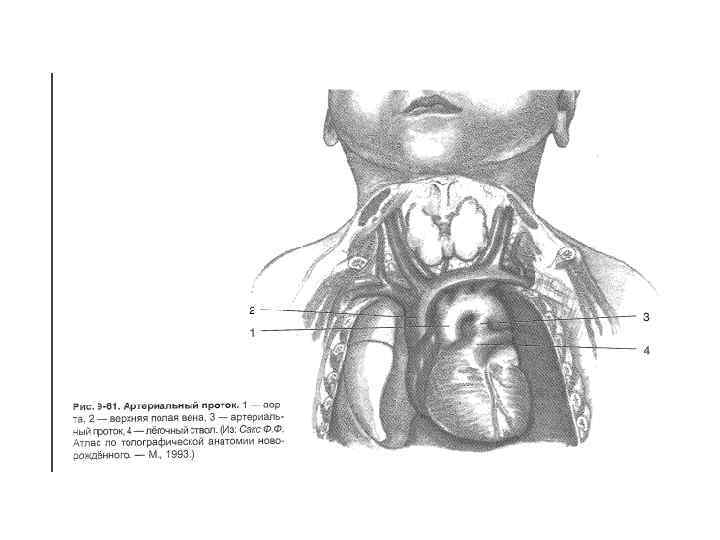

Перевязка открытого артериального протока 2 типа вмешательств: 1) Пересечение и ушивание протока 2) Введение в проток закупоривающей просвет пробки Операция показана в возрасте от 3 до 15 лет

Перевязка открытого артериального протока 2 типа вмешательств: 1) Пересечение и ушивание протока 2) Введение в проток закупоривающей просвет пробки Операция показана в возрасте от 3 до 15 лет